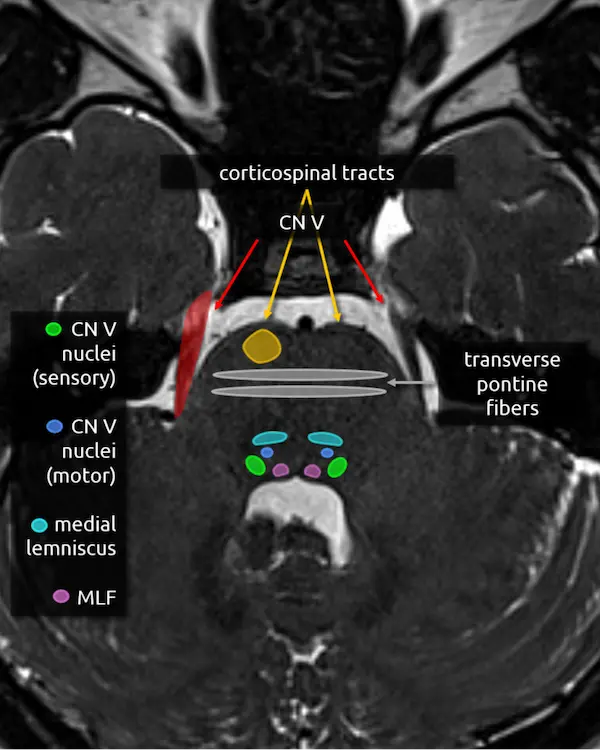

1. Corticospinal tracts

2. Superior cerebellar peduncles

3. Middle cerebellar peduncles

4. Transverse pontine fibers

5. Medial lemniscus

6. Medial longitudinal fasciculus (MLF)

2. Transverse pontine fibers

3. Medial lemniscus

4. Medial longitudinal fasciculus (MLF)

5. Trigeminal nerve (CN V)

The trigeminal nerve is the largest cranial nerve. It exits the side of the pons approximately one slice above the internal auditory canals, then curves forward to traverse the CSF space in front of the pons called the prepontine cistern. It primarily provides sensory innervation to the face, mouth, anterior two thirds of the tongue, nasal sinuses, and dura mater. It has a smaller contribution to motor function of the muscles of mastication.

The trigeminal nerve is large enough to be at least partially visible on routine brain MRIs, though it is sometimes cut off or volume averaged along its course. Notice the image below looks slightly different. This is a heavily T2-weighted sequence with thin slices that is designed to maximize the contrast between CSF and CSF-surrounded structures, usually cranial nerves, blood vessels, or extra-axial lesions. These heavily T2-weighted sequences are useful for ruling out the most common identifiable cause of trigeminal neuralgia: compression by a blood vessel (i.e. neurovascular compression). The region of a cranial nerve most susceptible to symptomatic compression is called the transition zone (aka Obersteiner-Reidlich zone), which is a few millimeters-long gradient of transition from oligodendrocyte myelination (central) to Schwann cells (peripheral). These transition zones are close to where the nerve emerges from the brainstem, called the root entry zone. For the trigeminal nerve, it is 3-4 mm away.

The trigeminal nerve has four nuclei, and two are located around this level.

6. Main sensory nucleus of the trigeminal nerve (CN V)

The main sensory nucleus of the trigeminal nerve is located in the posterolateral pons near the margin of the fourth ventricle approximately one slice above the internal auditory canals.

Lesions in this area will cause ipsilateral sensory loss of the face. A small white matter tract that carries pain and temperature sensation to the body, called the spinothalamic tract (see level 5), is in this region and may be damaged at the same time, resulting in an ipsilateral facial sensory deficit and contralateral body sensory deficit.

7. Motor nucleus of the trigeminal nerve (CN V)

The motor nucleus of the trigeminal nerve is small and located anterior and medial to the main sensory nucleus. As mentioned above, it provides motor innervation to the muscles of mastication primarily, but also to some smaller muscles in the ear and face, for example the tensor tympani muscle and tensor veli palatini.

Damage here may be detectable as weakness and deviation of the mandible or atrophy of the ipsilateral muscles of mastication.